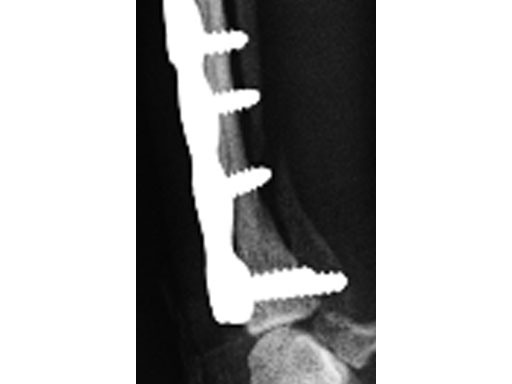

A 1-year-old female Yorkshire Terrier (1.7 kg) fractured the right distal radius and ulna (similar to a Colles fracture in humans). Open reduction and internal fixation was performed using a 7-hole 2.0 mm VET LCP notched head T-plate (a 7-hole plate was cut to eliminate the proximal two combination holes). The fracture was reduced and the distal bone fragment secured with two locking screws; the notch in the T-plate allowed independent contouring of this portion of the plate adjacent to the articulation. Compression was then applied across the fracture by loading one screw (second screw-hole proximal to the fracture); a second standard screw was then secured adjacent to the fracture (angled away/proximal to the fracture). The remaining screws were placed in a locked fashion. Despite the attempt at anatomical reduction, a slight (~1 mm) step was observed in the craniocaudal reduction (Fig 3). No fixation was applied to the ulna. A soft, padded bandage was applied to the forelimb (distal to the elbow joint) for minimal support and to control swelling.

The dog was discharged from the hospital 2 days postoperatively with instructions for strict exercise restriction; the dog was ambulatory on all four limbs at this time, although lame on the right forelimb. The bandage was to be removed in about 57 days. The dog did very well and was reevaluated 8 weeks postoperatively, at which time radiographs revealed a healed radius and atrophic ulna (Fig 4 - the ulnar atrophy is the norm in the canine for this repair in these small dog breeds). The dog was fully ambulatory and without lameness at this time; however, there was a slight decrease in full flexion at the antebrachiocarpal jointagain, this is the norm with this repair due to the surgical dissection and plate placement under the extensor tendons, which does not cause any functional deficit in the dog. The dog was gradually returned to full activity over the ensuing 2 weeks. It is recommended that these dogs not be allowed to jump from heights (eg, bed, chair) as they are at increased risk for this fracture, regarding the opposite limb in this patient.